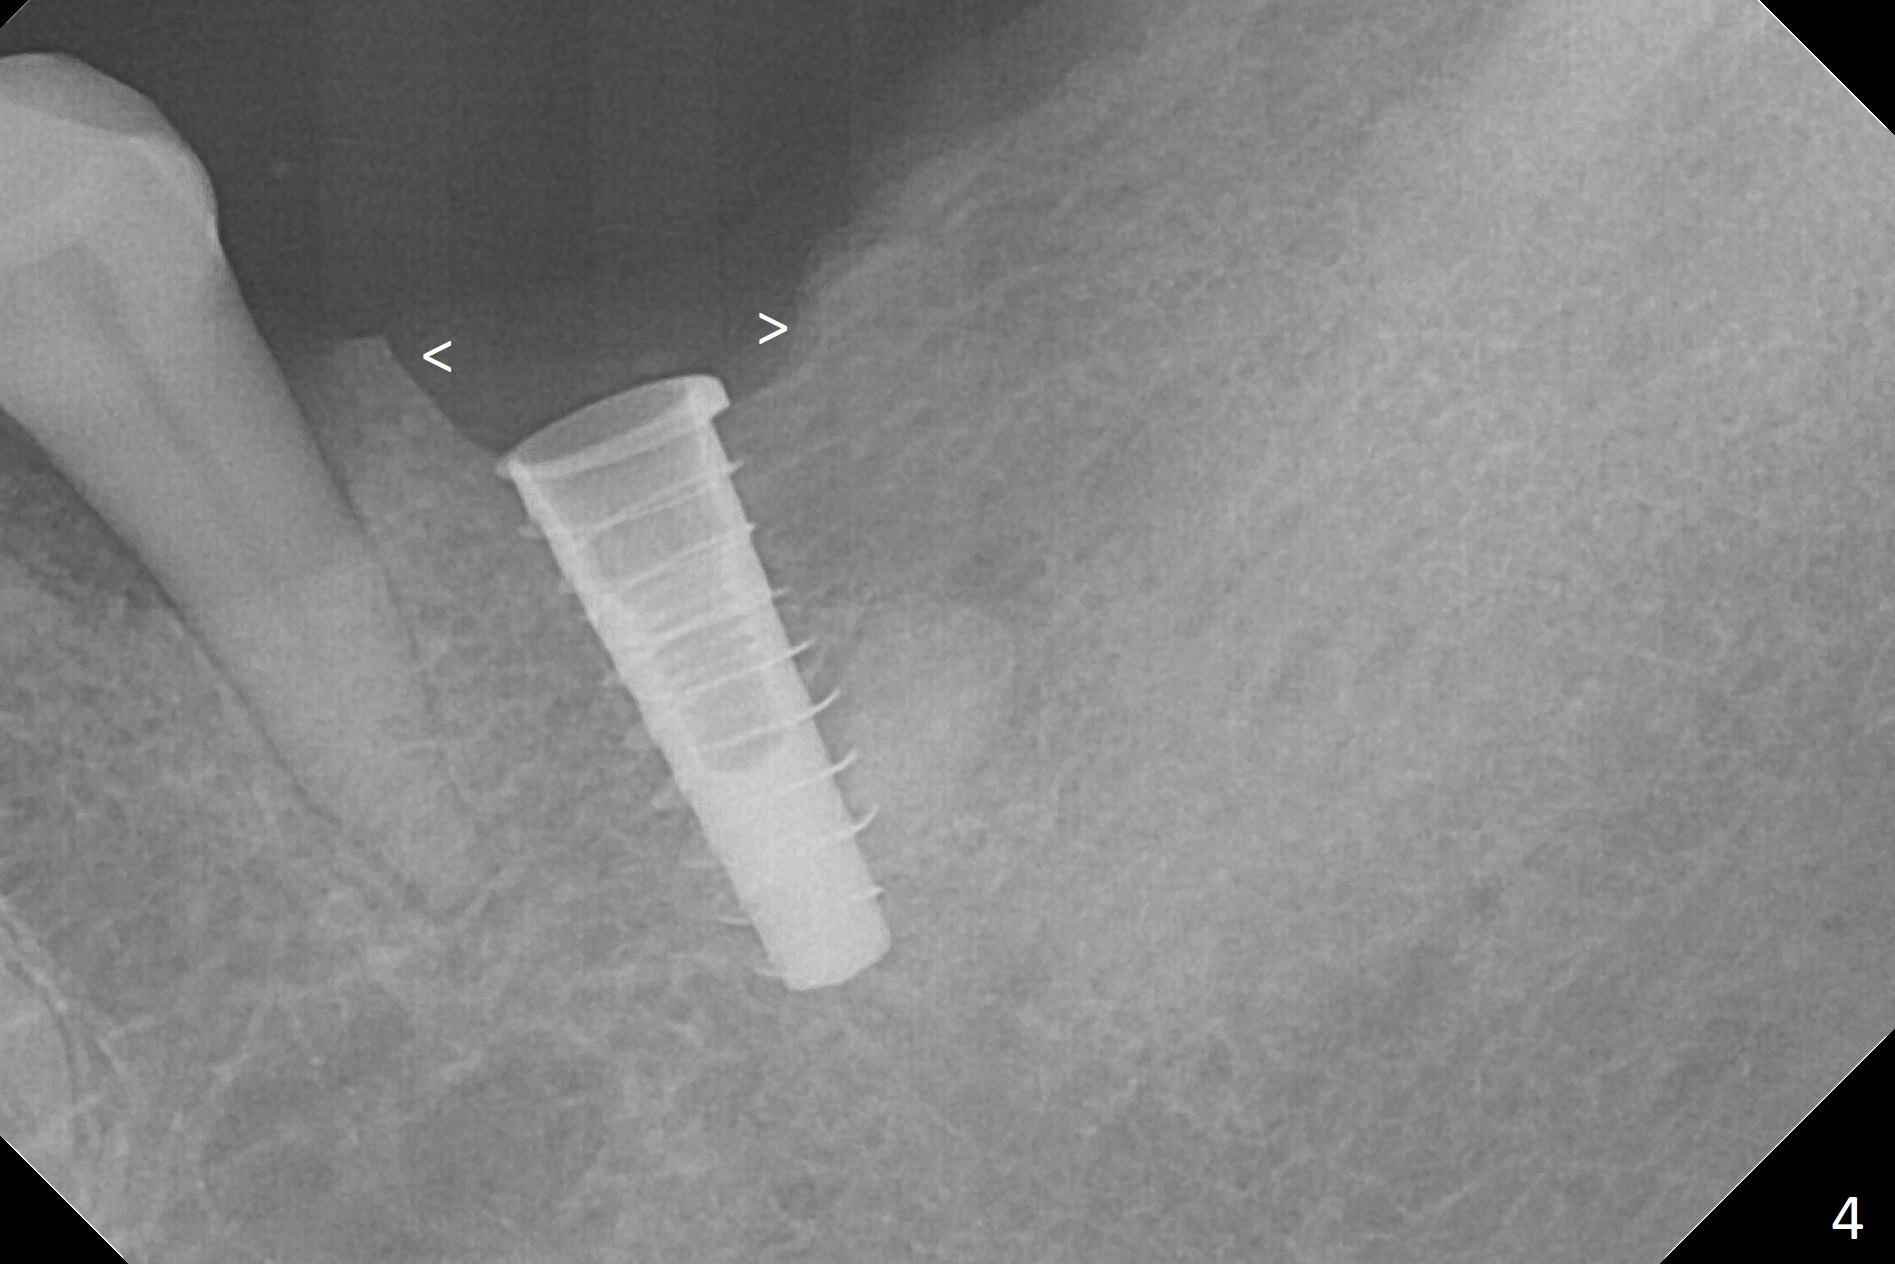

After incision over the narrow ridge at #30 (Fig.1) and ridge reduction (Fig.2 black area on the top; Fig.4 arrowheads), a 1.6 mm drill is used (Fig.2 (CBCT coronal section) long vertical black area) to start BEB (bone expansion and Bending). It is expected that the cortical and cancellous bone of the buccal (B) and lingual (L) plates can be expanded after use of Magic Expanders (ME) and 1.6 mm drill alternatively. In fact it appears that only the cancellous bone is pushed after MEs from 3 to 4.3 mm (Fig.3 arrows). There is no apparent cortical bone bending. There may be cancellous bone condensation. Dummy (Fig.4) and definitive (Fig.5) implants (4x11 mm) are placed. Since torque is 20 Ncm, a 5.5x4 mm healing abutment is placed (Fig.5,6 H). The opposing tooth is supraerupted; intrusion is pending. A 6x4(2) mm abutment is placed with a provisional 2 months postop. There is enough occlusal clearance. Impression is taken 5 months postop with difficulty because of subgingival margin (Fig.7). After cementation, the patient feels discomofort, which is relieved when the mesial embrasure is enlarged. Return to Lower Molar Immediate Implant, Armaments Xin Wei, DDS, PhD, MS 1st edition 12/14/2017, last revision 09/16/2018